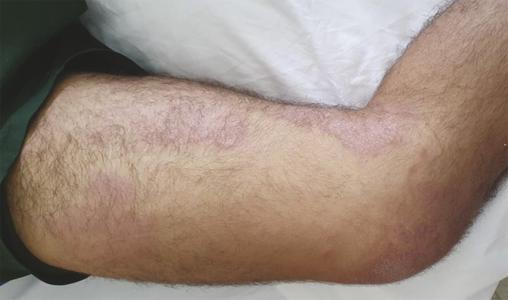

Lésions maculo-papuleuses prurigineuses au niveau des membres inférieurs  révélant une lèpre.

Extrait de : Œdèmes des membres révélant une lèpre